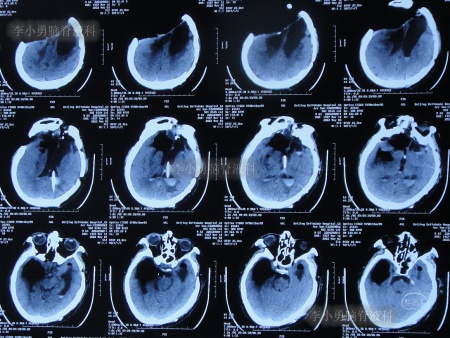

为求进一步治疗,2022年4月29日,第2次来李小勇脑脊液科治疗。入院时:意识不清,刺痛后四肢能动(图-31),查头颅CT(图-32)示脑室有扩张,有积气。

图-32:2022年4月29日头颅CT

入院后当天进行了原分流管拔除术+脑室引流术,术后当天查头颅CT示有出血(图-33)。

图-33:2022年4月29日术后头颅CT

术后5天即2022年5月3日,查头颅CT示脑室有缩小(图-35)。

图-35:2022年5月3日头颅CT

2022年5月13日(入院治疗15天),查头颅CT示脑室又有缩小(图-36)。

图-36:2022年5月13日头颅CT

2022年5月23日(入院治疗25天),查头颅CT示脑室缩小(图-37)。

图-37:2022年5月23日头颅CT